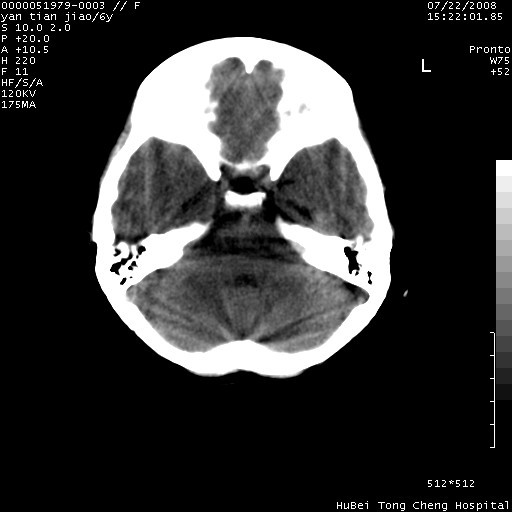

患儿 女,6岁。发热三天,昏迷五小时伴抽搐一次入院。pe:神志不清,浅昏迷状,双侧瞳孔不等大(右侧瞳孔直径3.5mm,左侧瞳孔2.0mm),对光反射迟钝,项强约一指,脑膜刺激征及病理反射阳性;双肺可及痰鸣音;四肢肌张力不高。

临床诊断:病毒性脑膜脑炎并脑疝?

颅脑ct轴位平扫,如下图:

大面积低密度区,可疑脑炎,建议强化!

结合临床症状,符合右颞顶枕叶病毒性脑膜脑炎.建议增强或mri。

右侧低密度区结合临床考虑脑炎